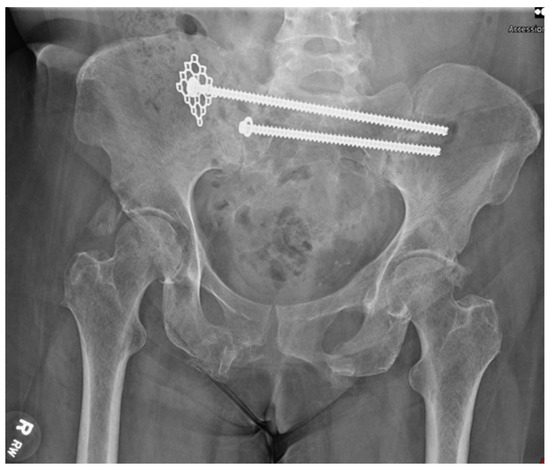

Figure 5.

AP pelvis demonstrating trans-iliac trans-sacral screw placement at the S1 and S2 level with the use of a midfoot plate as a washer on the S1 screw.

Prior lateral hip incisions were reopened and enlarged to gain access to the posterior sacral hardware. Both existing screws were recannulated with wires, and the S2 screw was removed and replaced with a new Synthes 130 mm fully threaded 7.3 mm cannulated screw, which achieved moderate purchase. The S1 screw was removed; however, the standard washer was determined to be too small, risking propagation of the fracture. Instead, a mesh plate from the Synthes Variable Angle Midfoot set was chosen to act as the washer and cut to 3 × 3 holes. The larger surface area of the mesh plate allowed for increased bony interface of the construct, thus distributing the forces and decreasing the risk of fracture propagation while also increasing stability. The middle hole of the plate was placed over the S1 wire, followed by a standard washer, and the Synthes 165 mm fully threaded 7.3 mm cannulated screw (Figure 5). This combination of hardware achieved excellent purchase and re-established stability of the right posterior pelvis. Alignment was confirmed with intraoperative fluoroscopy. There were no obvious perioperative complications, and the patient was transferred to the PACU.